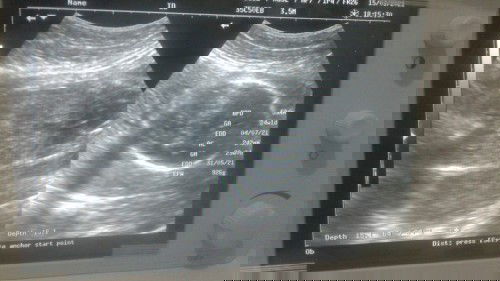

Usia kandungan sudah 8bln 10minggu tapi sama sekali belum menyiapkan keperluan si dedek 😣.. suwami bingung haru gimana kerjaan susah buat makan sehari" sudah ada alhamdulilah, , tpi iri lihat orang" yng baru 7bln udah lengkap buat dedeknya Semoga aja sebelum hari H bisa beli perlengkapan baby amin" #bantusharing #jangandibully